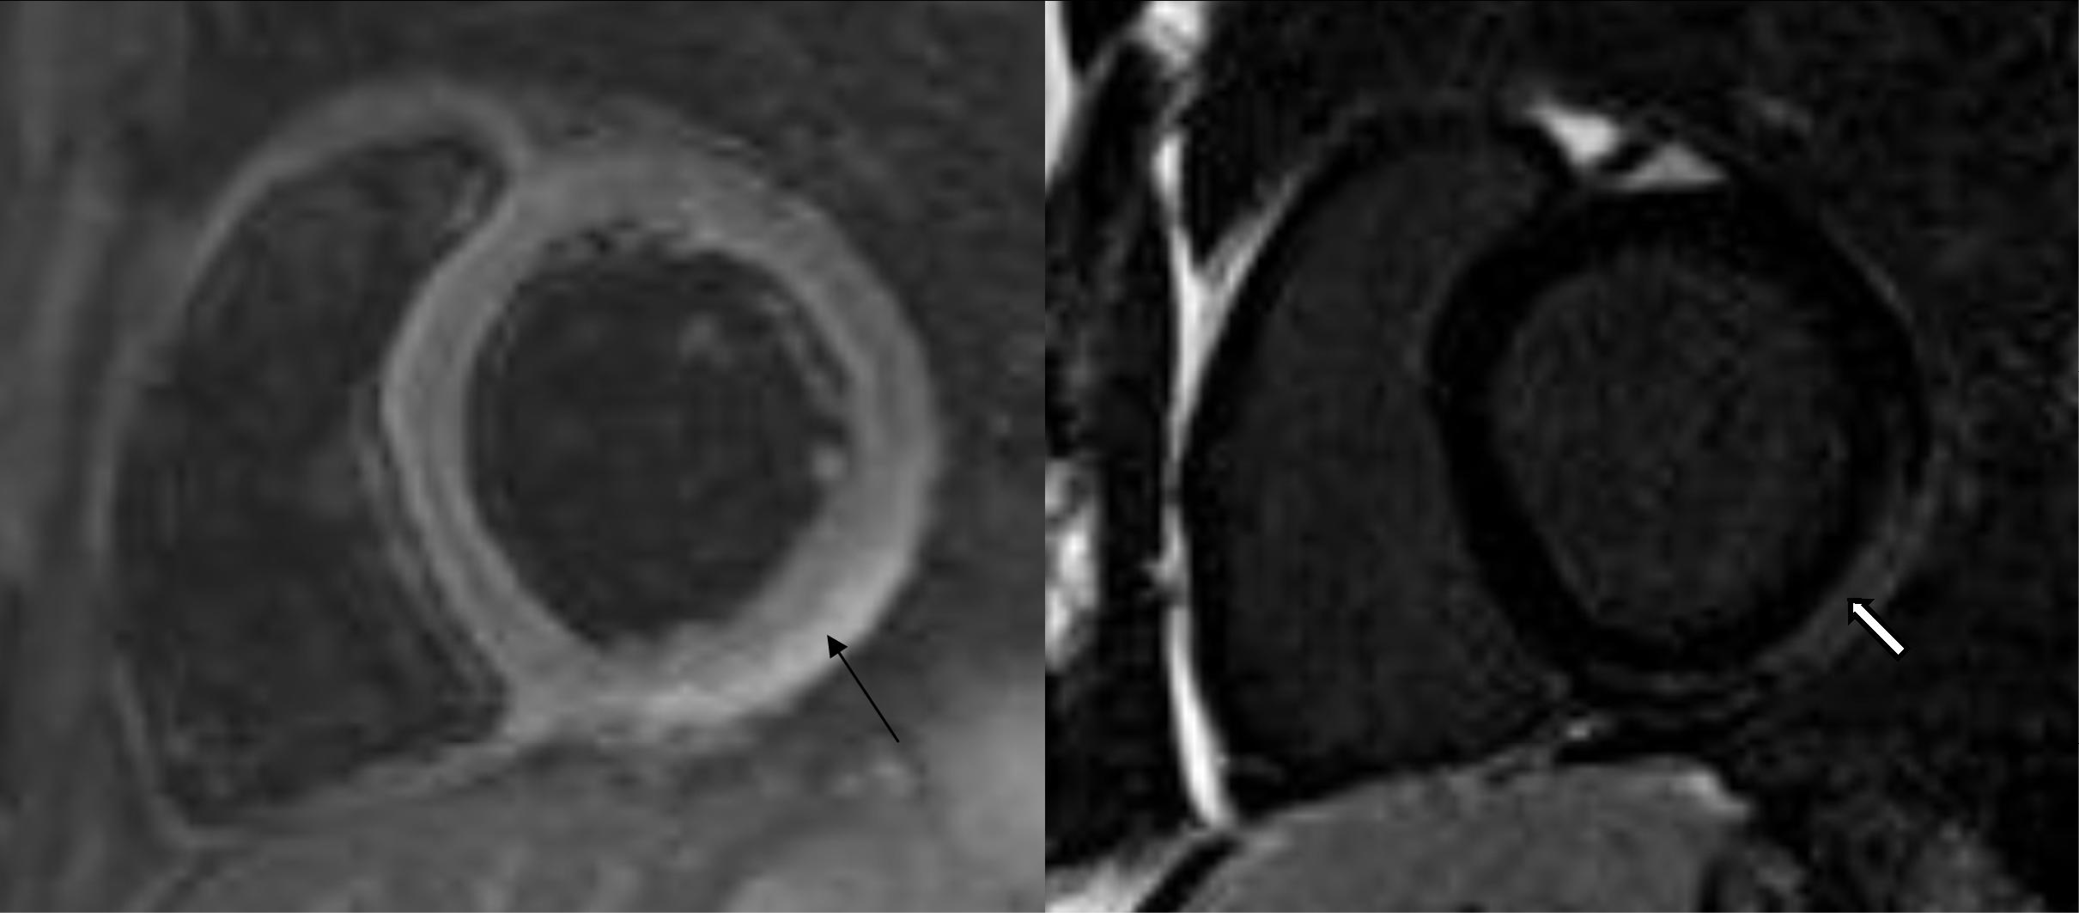

COVID-19 may result in a number of complications ranging from mild to very severe cases. It is estimated that 17–29% of patients develop acute respiratory distress syndrome (ARDS).6 Although the disease mostly affects the respiratory system, complications may influence any other system. Commonly reported sequelae are acute cardiac injuries. The mechanism of cardiovascular injury from COVID-19 has not been completely explained and could be a complex phenomenon. However, it manifests itself by myocardial ischemia and cardiac arrest. Recent works describe not only elevated troponin levels, but also myocardial ischemia and cardiac arrest associated with COVID-19 infection.25 The authors of the editorial entitled “Coronavirus disease 2019 (COVID-19) and the heart – Is heart failure the next chapter?” point to various cardiac complications after pneumonia.26 The diagnosis of cardiovascular disease (CVD) complications should be based on examination, symptoms, elevated cardiac markers, and electrocardiography (ECG). However, when the patient’s condition is not stable, further steps must be taken, including medical imaging27 (e.g., a CT scan28). A severe COVID-19 complication is myocarditis (Figure 7). Puntmann et al. suggest that approx. 60% of patients could experience myocardial inflammation, with no association to preexisting conditions or the severity of COVID-19.29 When myocarditis is suspected, the examination that should be taken into consideration is cardiac magnetic resonance (CMR).29 It is confirmed that SARS-CoV-2 infection increases the risk of pulmonary embolism (Figure 8) and deep vein thrombosis.30 When acute thromboembolic disease is suspected, not only should D-dimer levels be tested, but an assessment via computed tomography angiography (CTA) is essential.31